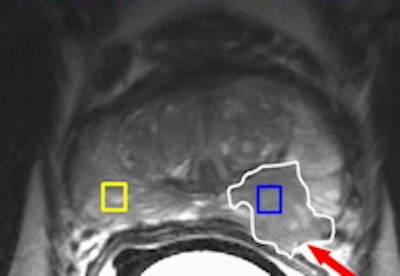

A 56-year-old male with prostate-specific antigen (PSA) level of 11; transrectal ultrasound (TRUS) biopsy, Gleason 3+4 left; DRE T1c. Prostatectomy confirmed Gleason 4+3 prostate cancer (PC) with extracapsular extension (ECE) in left peripheral zone (PZ). Left: Axial T2-weighted MR image shows low-signal lesion in the left PZ (white outline), which fits PC with ECE (arrow, PI-RADS 5). Right: Axial dynamic contrast-enhanced MR image shows asymmetric focal enhancement both in tumor in left PZ, with curve type 3 (PI-RADS 5). All images courtesy of Dr. Jelle Barentsz.Evidence is growing that MRI before the second, or even initial, biopsy can accurately distinguish between those patients who require immediate biopsies and those for whom biopsy can be deferred. A correlation between apparent diffusion coefficient (ADC), calculated from DWI, and Gleason score has been found. MRI before biopsy can help to detect high-grade tumors, which helps target biopsies within areas of low ADC values.